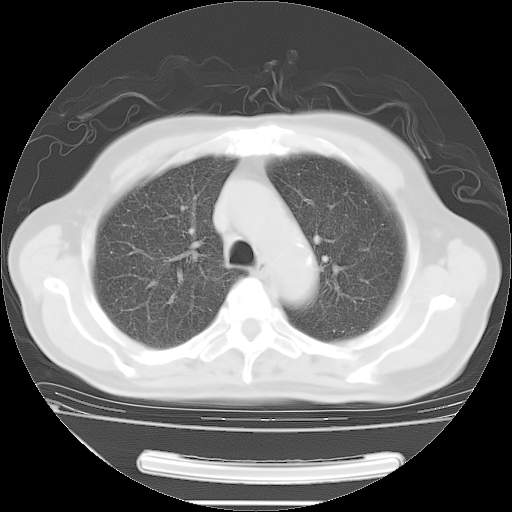

今天复查肺部CT,发现双肺广泛磨玻璃样改变。所以我把3月19日和5月9日相隔50天的肺部CT上传。请大家会诊。

2009年3月19日肺部CT片。

2009年3月19日肺部CT